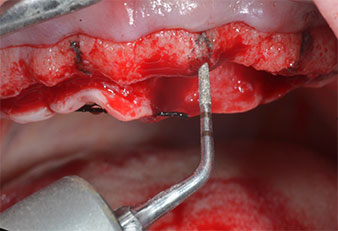

Фиг. 2 След инцизия в средата на алвеоларния гребен и препариране на мукопериостални ламба, позициите на имплантите са трансферирани в костта.

Пиезоелектрически инструмент с диамантено покритие с форма на пламък (Piezomed I1) e използван за маркиране на позициите на имплантите и за пилотна подготовка (Фиг. 3). Препарацията беше извършена с внимателни вертикални движения, с намалена мощност, пълна иригация и лек натиск (под 300 g) След това се приложи пилотен инструмент (Piezomed I2A/ I2P) за първоначално увеличение на диаметъра на имплантното ложе с 2 mm (Фиг. 4), последвано от 3 mm разширение (Фиг. 5)

Фиг. 3 Препарацията с ултразвуков пилотен накрайник I1 се извършва с движение нагоре-надолу, успоредно с дългата ос на работната част.